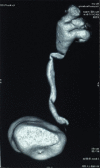

Genitourinary tract arteriovenous malformations are extremely rare. Most of the lesions are found either in the kidney or urinary bladder. So far, to the best of our knowledge, only five cases of arteriovenous malformation of the ureter have been reported in the literature. Here, we present, a young male, clinically presented with pain in the left flank with no other significant history. On radiological evaluation found to have left hydroureteronephrosis with stricture of the left distal ureter at the level of iliac vessel crossing. Urine routine, cytology, and cystoscopy were unremarkable. Left retrograde pyelogram showed distal ureteric stricture. Patient underwent excision of left distal ureteric stricture segment and ureteric reimplantation with psoas hitch. Histopathological examination revealed the features of arteriovenous malformation of the left ureter. The patient is asymptomatic and has no recurrence on follow-up until 12 weeks after surgery.